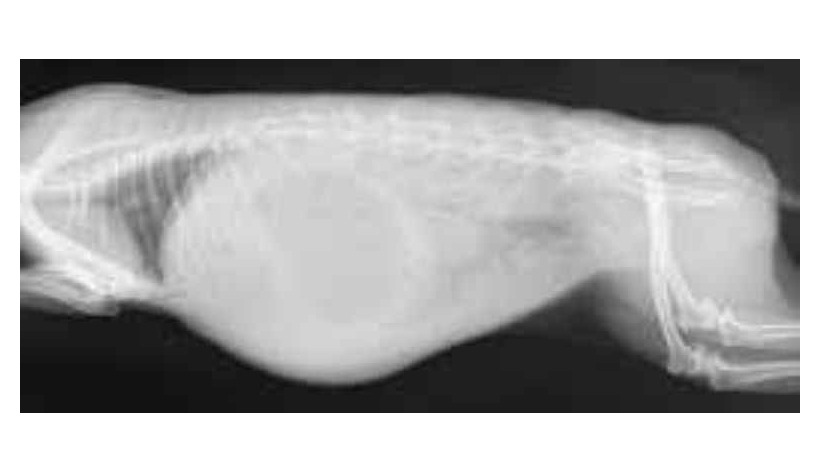

Mercredi 20 Mars 2024 Animaux de compagniePhoto n° 1 : Radiographie de profil d'un lapin en occlusion : image caractéristique de l'estomac dite en oeuf au plat.

© FauneVet